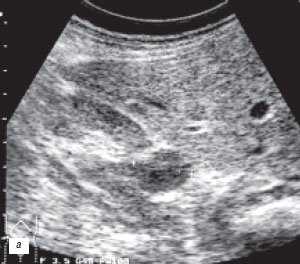

(Слева) УЗИ, продольная плоскость сканирования: гипоэхогенное «объемное образование» в центре, которое выступает в почечную лоханку.

(Справа) КТ с контрастированием, аксиальная проекция: у этого же пациента установлено, что «объемное образование» — это нормальное корковое вещество почки, которое инвагинирует в почечную лоханку между чашечками верхнего полюса и меж полюсной областью почки. Обратите внимание на нормальный внешний контур почки. Бертиниевы колонны чаще всего выявляют с одной стороны и слева, как в данном случае: в 18% случаев они могут быть двусторонними.